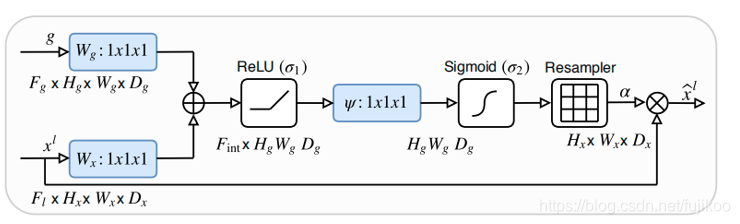

AG的原理如下图:

其中g为门控信号,xl为encoder对应的feature map,g来自于decoder的下一层,所以g尺寸大小是这一层的1/2。x完成Attention之后和g一起concat再进入下一层decoder。

在上面这个图中,黄色的xl如果在unet中是要直接通过跳跃连接和绿色的g上采样的结果进行concat,但是在attention unet中先对xl和g转成一样的size,然后相加经过relu、sigmoid得到attention coefficients。

论文中作者说要结合上下文的信息,上文指的是encoder中的xl,下文指的是xl对应的decoder中的下一层,由于g更深,学到的东西更多,信息更准确。g里面含有的信息,可以当做注意力要去学习的方向。最后让xl与attention coefficients相乘,相乘就是把g里的信息叠加到xl,就能把注意力放到目标区域上了,再通过训练使得attention coefficients的让注意力更集中,让target区域的值趋近1,不相关的区域趋近0。

可以理解成如果直接将g上采样一次得到g’,g’和xl的size一样。那么同样是target的区域的像素值,g’里的像素值会比xl里的像素值大,和xl叠加,就相当于告诉了xl应该去学习的重点。